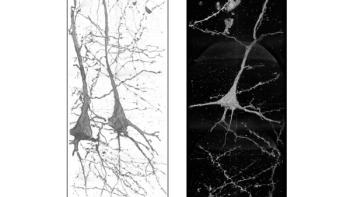

High resolution, 3D images reveal differences in the structure of neurons from healthy brains and those from patients with schizophrenia.